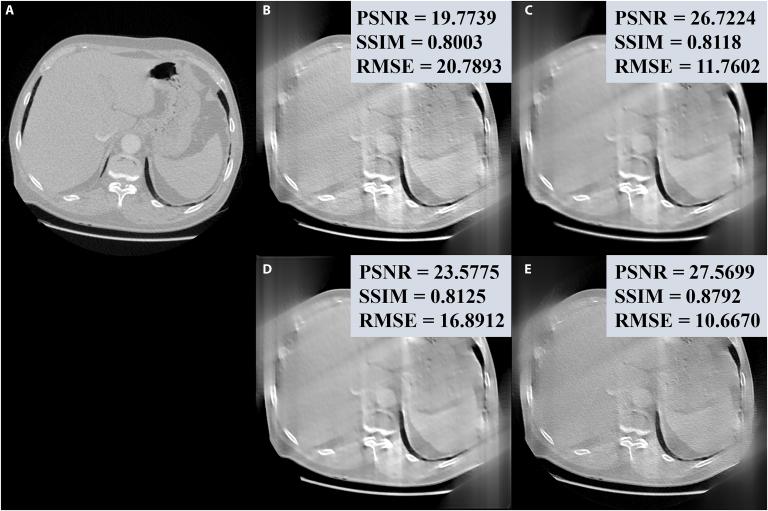

With the increasing use of computed tomography (CT), concerns about radiation dose have grown. Deep-learning-based methods have shown great promise in improving low-dose CT image quality while further reducing patient dose. However, most deep-learning-based methods are trained on vendor-specific CT datasets with varying imaging conditions and dose levels, which results in poor generalizability across vendors due to marked data heterogeneity. Moreover, the centralization of multicenter datasets is restricted by the high costs of data collection and privacy regulations. To overcome these challenges, we propose FedM2CT, a federated metadata-constrained method with mutual learning for all-in-one CT reconstruction. This method enables simultaneous reconstruction of multivendor CT images with different imaging geometries and sampling protocols in one framework. Specifically, FedM2CT consists of 3 modules: task-specific iRadonMAP (TS-iRadonMAP), condition-prompted mutual learning (CPML), and federated metadata learning (FMDL). TS-iRadonMAP performs task-specific low-dose reconstruction, CPML shares condition-prompted knowledge between clients and the server, and FMDL aggregates model parameters with a metamodel to effectively mitigate the effect of data heterogeneity. Extensive experiments under 3 different settings demonstrate that the proposed FedM2CT achieves outstanding results compared to other methods, both qualitatively and quantitatively, showing the potential to achieve the goal of all-in-one CT reconstruction with different low-dose tasks, i.e., low-milliampere-second, sparse-view, and limited-angle.

随着计算机断层扫描(CT)的使用日益增加,对辐射剂量的担忧也与日俱增。基于深度学习的方法在提高低剂量CT图像质量的同时进一步降低患者剂量方面显示出巨大潜力。然而,大多数基于深度学习的方法是在具有不同成像条件和剂量水平的特定厂商CT数据集上进行训练的,由于显著的数据异质性,这导致跨厂商的泛化能力较差。此外,多中心数据集的集中化受到数据收集高成本和隐私法规的限制。为了克服这些挑战,我们提出了FedM2CT,一种用于一体化CT重建的具有相互学习的联邦元数据约束方法。该方法能够在一个框架中同时重建具有不同成像几何形状和采样协议的多厂商CT图像。具体而言,FedM2CT由3个模块组成:特定任务的iRadonMAP(TS-iRadonMAP)、条件提示相互学习(CPML)和联邦元数据学习(FMDL)。TS-iRadonMAP执行特定任务的低剂量重建,CPML在客户端和服务器之间共享条件提示知识,FMDL使用元模型聚合模型参数以有效减轻数据异质性的影响。在3种不同设置下进行的大量实验表明,与其他方法相比,所提出的FedM2CT在定性和定量方面均取得了出色的结果,显示出实现不同低剂量任务(即低毫安秒、稀疏视图和有限角度)一体化CT重建目标的潜力。